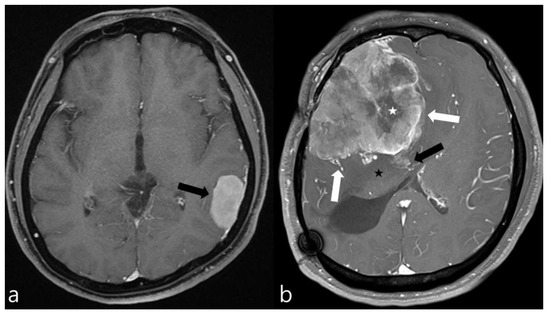

2.3. Radiologic Evaluation

Figure 1. Contrast-enhanced axial MR images of two meningiomas. (a) This image exhibits the typical features of a low-grade meningioma, including homogeneous enhancement, smooth margins, absence of peritumoral edema, and no significant mass effect on the surrounding brain parenchyma (black arrow). (b) In contrast, this image displays the hallmarks of a high-grade meningioma, characterized by necrotic areas (white asterisk), pronounced mass effect, peritumoral edema (black asterisk), irregular margins (white arrows), and suspicious invasion into the adjacent brain parenchyma (black arrow), indicating a more aggressive tumor behavior.